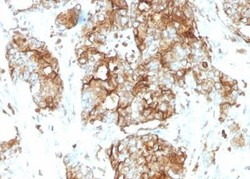

- Submitted by

- Novus Biologicals (provider)

- Main image

- Experimental details

- Immunohistochemistry-Paraffin: CEACAM5/CD66e Antibody (SPM584) - Azide and BSA Free [NBP2-34851] - Human Colon Carcinoma stained with CEACAM5/CD66e Antibody (SPM584).